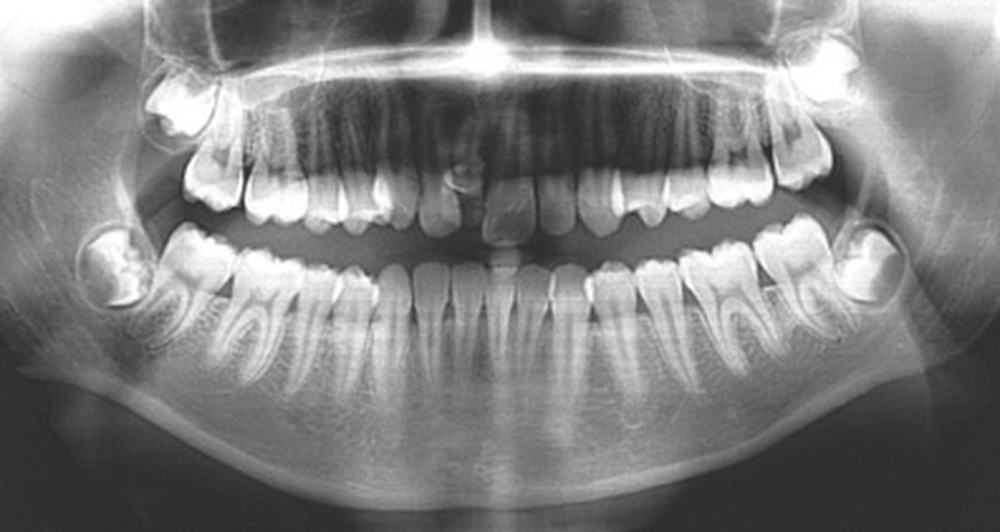

D’un point de vue occlusal, le patient, en denture adulte jeune stable, présente une classe II d’Angle bilatérale de 4 mm, associée à un encombrement maxillaire de 5 mm et mandibulaire de 2 mm. La face mésiale de 21 est centrée avec le plan sagittal médian, la non-concordance des médianes incisives est d’origine mandibulaire (déviation de la médiane mandibulaire vers la gauche) (fig. 1b-d).

Son incisive centrale supérieure droite (11) présente un défaut de structure amélaire sévère, compromettant une technique restaurative pérenne a minima. L’examen de la panoramique (fig. 1e) et de la radiographie rétroalvéolaire de 11 (fig. 1f) objective une fracture coronaire verticale, ainsi qu’une racine grêle et courbe, peut-être en rapport avec un ancien traumatisme [1]. Le rapport couronne clinique/racine clinique est défavorable.

L’analyse de la téléradiographie de profil (fig. 1g) confirme une classe II squelettique à tendance hyperdivergente avec une normo-position de l’incisive mandibulaire dans sa symphyse. L’âge du patient et la croissance mandibulaire en rotation postérieure (travaux de Björk) ne permettront sans doute pas une correction de la classe II squelettique sans version de l’incisive mandibulaire.